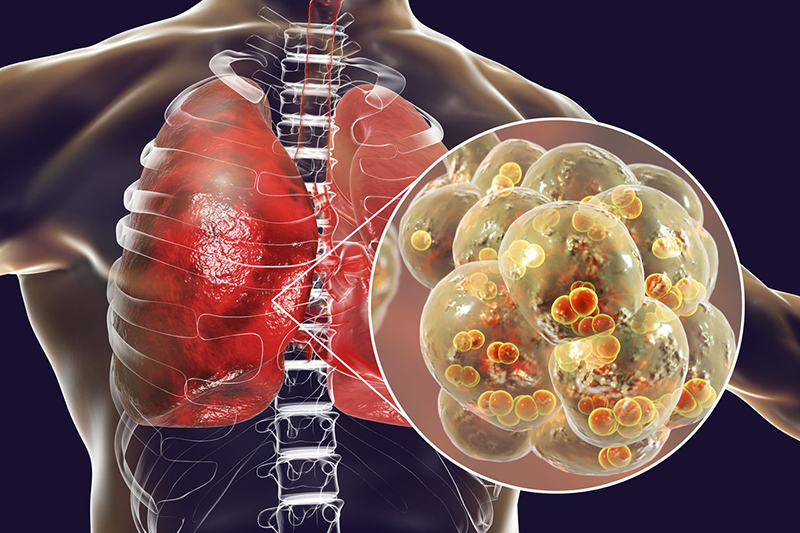

I. Viêm phổi là gì?

*Viêm phổi được định nghĩa là sự viêm và đông đặc nhu mô phổi do tác nhân nhiễm trùng như vi khuẩn, siêu vi, ký sinh trùng, nấm. Có 2 dạng viêm phổi phổ biến, đó là:

- Viêm phổi xuất hiện ngoài bệnh viện: Đây là tình trạng viêm phổi mắc phải ngoài cộng đồng (CAP: Community Acquired Pneumonia).

- Viêm phổi xuất hiện từ giờ thứ 72 sau nhập viện: Được gọi là viêm phổi mắc phải trong bệnh viện (HAP: Hospital Acquired Pneumonia) hay viêm phổi bệnh viện.